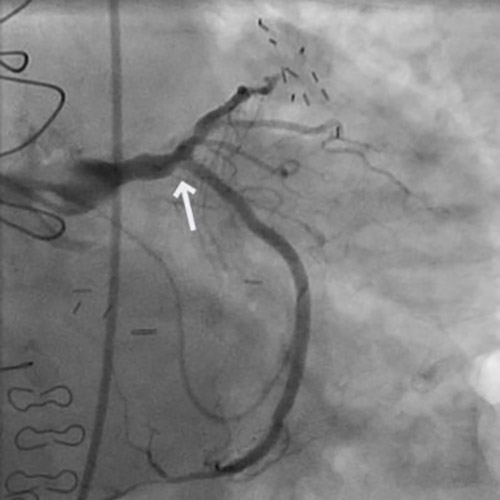

A 73-year-old male with a history of coronary artery bypass grafting (CABG), including patent LIMA to LAD, patent SVG to D2, and occluded SVG to OM, presented with unstable angina (UA).